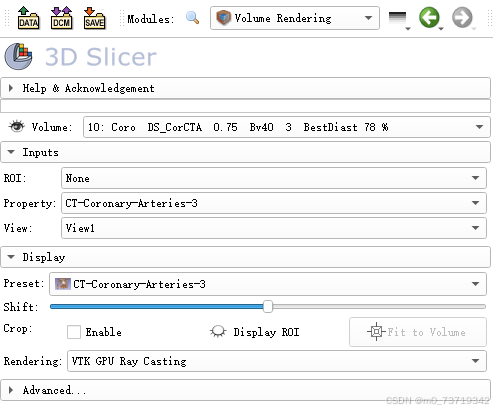

点击该按钮选择Volume Rendering

进行如下配置